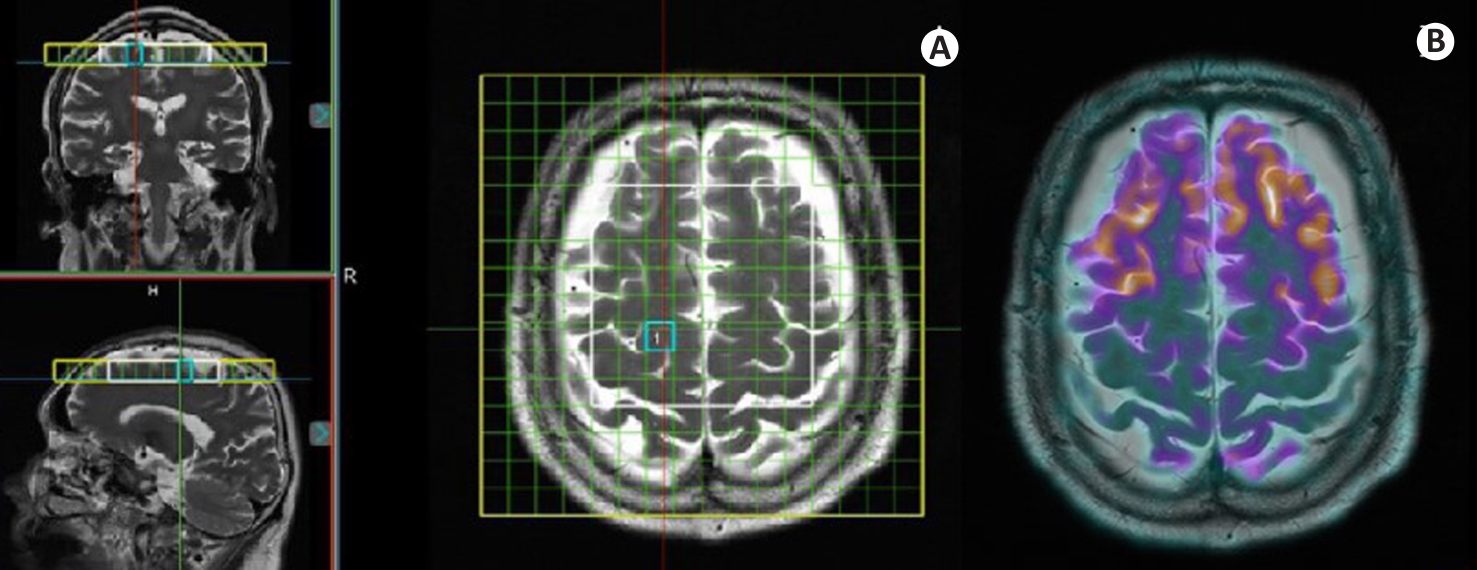

Fig.1 PET/MRS imaging of a female AD patient (76 years old, education years: 0; MMSE: 0; MoCa: 0; CDR: 3). A: Coronal, sagittal, and axial localization images of MRS acquisition site, where the yellow box indicates the homogenization region, the white box denotes the MRS acquisition area, and the blue box outlines the selected voxel. B: Co-registered PET/MR fusion image at the same level as the MRS acquisition.